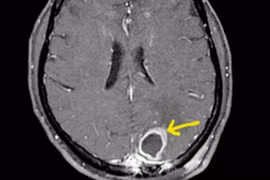

(GLO)- Bệnh viện Phong - Da liễu Trung ương Quy Hòa vừa điều trị thành công một trường hợp nhiễm vi khuẩn Whitmore nguy kịch với nhiều biến chứng nặng.

(GLO)- Trung tâm Kiểm soát bệnh tật Gia Lai vừa ghi nhận ca bệnh Whitmore đầu tiên trong năm 2026. Bệnh nhân là chị K.H (SN 1987, trú tại làng Mook Trang, xã Ia Dom), đang điều trị tại Khoa Hồi sức tích cực - chống độc, Bệnh viện Đa khoa Gia Lai.

Sau khi sốt cao 3 ngày, chị L. rơi vào suy hô hấp, sốc nhiễm khuẩn. Các bác sĩ phải can thiệp bằng ECMO để cứu người bệnh.